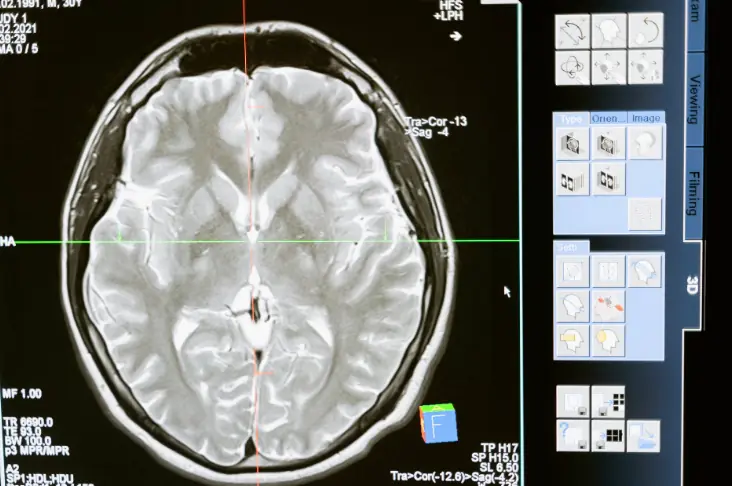

Each of the children were asked to lie in an MRI machine while being shown pictures of actors making "fearful" or "neutral".

Their brain activity was then mapped with the hope of being able to correctly identify patterns to distinguish who is smacked and who isn't.